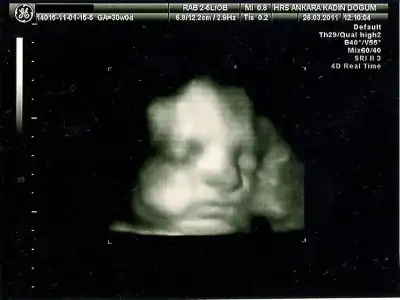

28.haftada bu kadarsa 4 kilo doğar maşallah